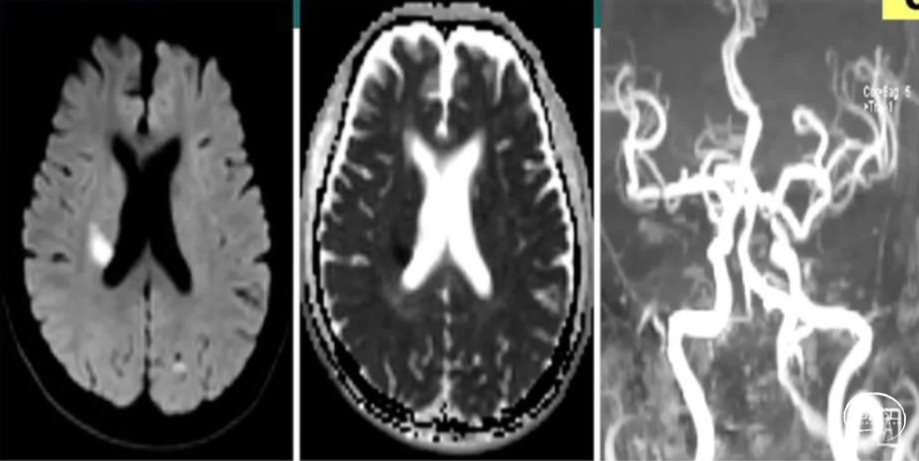

头颅MRI示:右侧脑室旁、基底节区急性脑梗死,

MRA示:右侧大脑中M1段局限性狭窄;